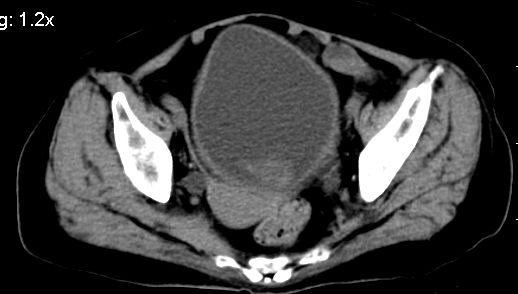

标题: CT10133:F、74岁,反复血尿10天。 [打印本页]

标题: CT10133:F、74岁,反复血尿10天。

膀胱充盈可,壁光滑厚薄尚均匀,其内下方可见不规则的致密影,建议做膀胱镜检查

膀胱癌突破浆膜可能性大

考虑膀胱癌可能性大伴双侧输尿管下端扩张.

膀胱后壁见不规则致密影,我们遇到这样的病人都再做一次俯卧位扫描;排出膀胱内凝血块。

1.膀胱后壁见不规则致密影,占位?膀胱内凝血块?建议俯卧位扫描、膀胱镜检查.

2.双侧输尿管下段扩张.

膀胱三角区不规整软组织改变,双侧输尿管扩张,所以占位性病变肯定首先考虑,建议改变体位扫描除外游离血块影,但老年人出血原因一定要查明。